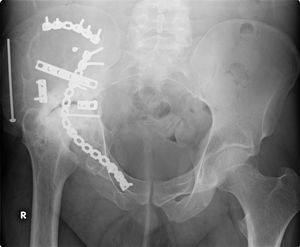

طب العظام يعنى بشكل عام بتصحيح الكسور جراحيا وتجبيرها إضافة إلى عمليات إصلاح وتبديل المفاصل التالفة. بالإضافة إلى أنواع أخرى من العمليات الجراحية التي تعالج أمراض العظام والجهاز الحركي.

جراحة العظام فرع من فروع الطب يعالج اعتلالات العظام والعضلات والأنسجة المتصلة بها. ويُدعى الأطباء الذين يُمارسون جراحة العظام جراحو العظام. وهم يُعالجون مُشكلات طبية كثيرة في هذا المجال منها الكسور، وإصابات الأوتار والأربطة، وتشوهات الأطراف والعمود الفقري. وقد توجد بعض الاعتلالات العظمية منذ الولادة، بينما تظهر اعتلالات أخرى أثناء الطفولة بسبب مشكلات تتعلق بالنمو، أو في فترة متأخرة من العمر نتيجة للشيخوخة. كما تحدث اعتلالات أخرى نتيجة إصابة ما أو مرض. ويُشكل المصابون في حوادث السيارات، أو الأنشطة الرياضية أو أثناء التنزه والاستجمام عددًا كبيرًا من المرضى الذين يعالجهم اختصاصيو العظام. ويصف الأطباء لمعالجة الاعتلالات العظمية الأدوية، والجراحة، والعلاج الطبيعي. وقد يقوم الاختصاصي، على سبيل المثال، بإجراء جراحة لتقويم كسر أو تشوه. وبعد الجراحة قد يستخدم الاختصاصي قالبًا أو مقبضًا، ويصف العلاج الطبيعي كي يساعد على الشفاء. مثل هذه المعالجة قد تشمل استخدام جهاز يطلق نبضات كهربائية تُساعد العظم على الالتئام. كما قد يقوم الاختصاصي بإجراء جراحة لاستبدال مفصل من البلاستيك أو المعدن أو من مواد أخرى بمفصل ملتهب، أو مصاب. والمفصل الذي يستبدل عادة أكثر من غيره، هو مفصل الورك.

- جراحة الإصابات